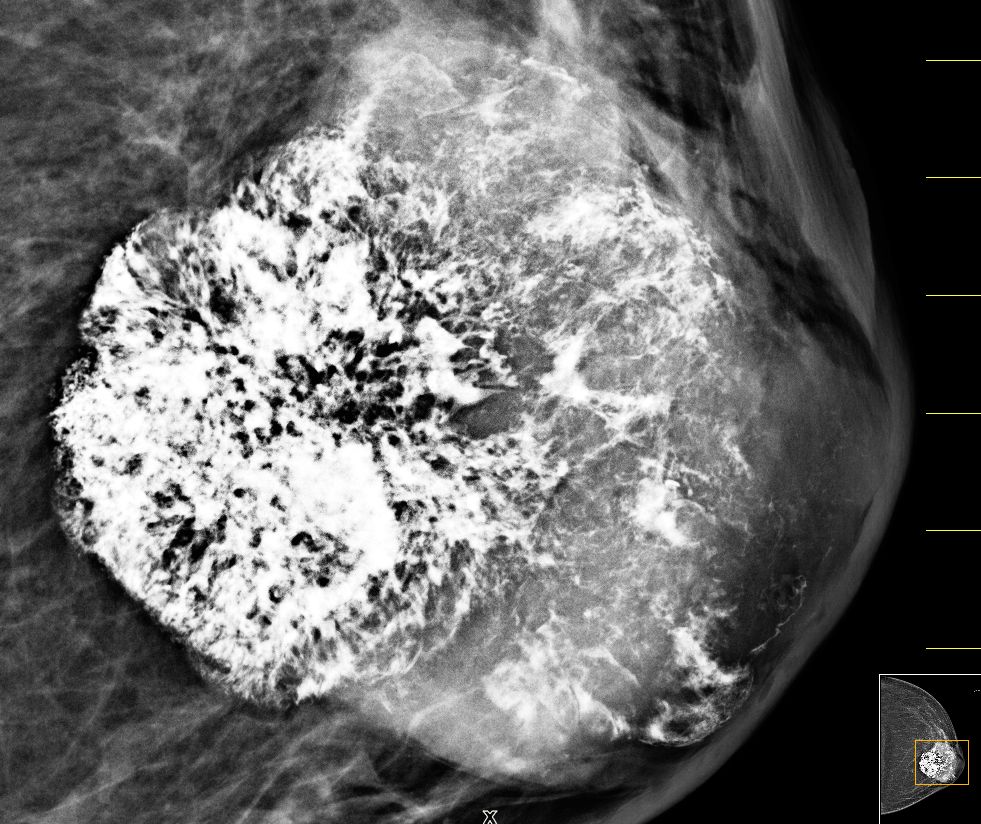

| Fall | 72-jährige Frau, bei der vor 5 Jahren ein gutartiger Tumor diagnostiziert wurde. Vor 8 Monaten war der Tumor auf 4cm angewachsen. Die Exzision wurde empfohlen. Jetzt war der Tumor 66 mm groß, sehr hart und teilweise verkalkt. | |||

| vor 8 Monaten | Mammographie links MLO.![]() |

Vergrößerung.![]() | ||